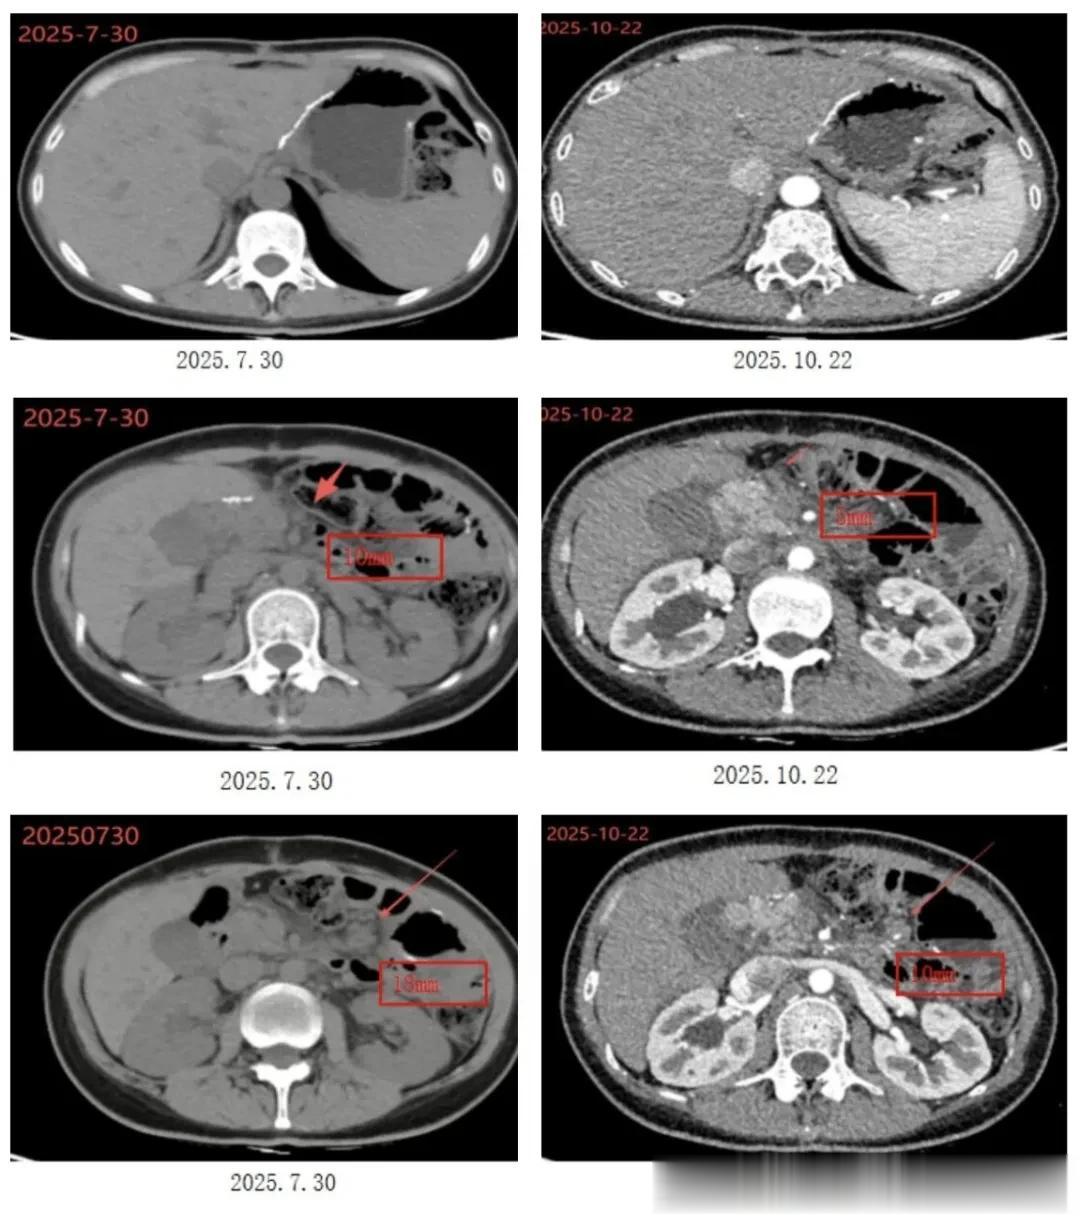

但即便已经使用了强化治疗手段,但治疗效力依然有限,2025年7月复查显示:部分胃壁局限性增厚,肠系膜根部、腹膜后脂肪间隙模糊伴多发淋巴结肿大,较大者直径约10mm,网膜周边多发淋巴结,较大者直径约18mm。

• 胃部情况:2025年10月22日,复查CT示:胃大部切除术后改变;

• 腹部情况:2025年7月30日至2025年10月22日,胸腹盆部CT示:肠系膜根部、腹膜后脂肪间隙模糊,多发淋巴结缩小从10mm→5mm;胸腹盆部CT示:网膜周边多发淋巴结缩小从18mm→10mm;

肿瘤标志物检测示:vNKT细胞治疗期间 CA19-9、CEA、CA72-4均在正常范围内。